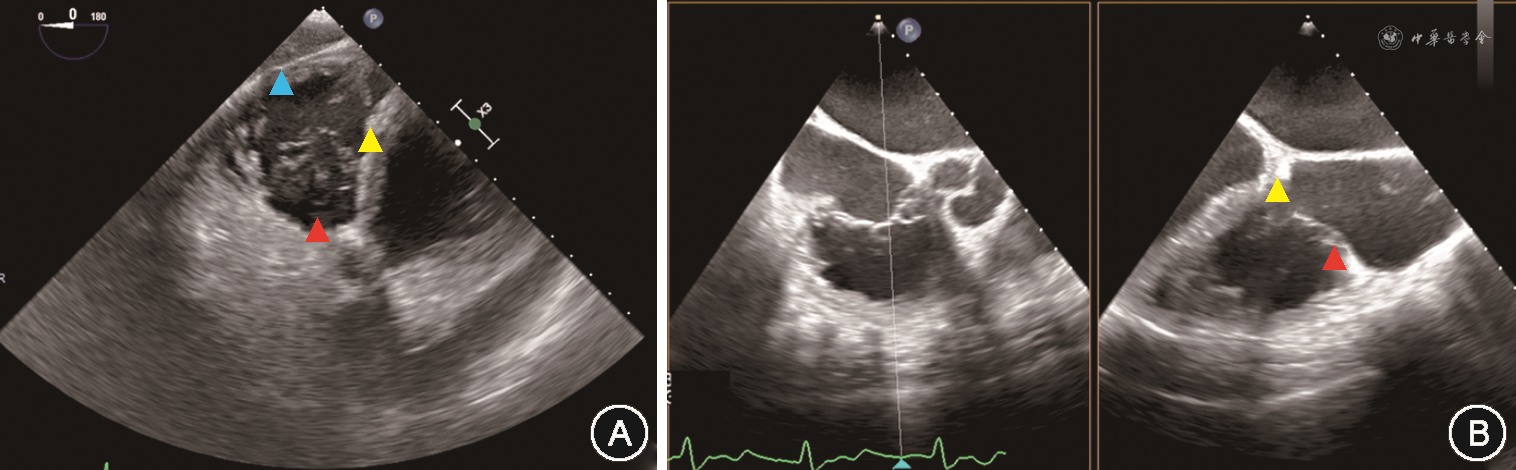

经导管三尖瓣缘对缘修复手术在全身麻醉、气管插管下进行。本研究所使用的经导管三尖瓣缘对缘修复器械为淇麟三尖瓣缘对缘修复系统(上海申淇医疗科技有限公司)、Neoblazar经导管三尖瓣夹合器及输送系统(江苏臻亿医疗科技有限公司)。本文所描述的手术过程以淇麟三尖瓣缘对缘修复系统为例。经右侧股静脉穿刺送入加硬导丝,在TEE 双腔切面引导下将导丝送入上腔静脉。使用18 Fr(1 Fr=0.33 mm)扩张子扩张股静脉穿刺处。将导引鞘头端调直,在TEE Bicaval View引导下沿导丝送入导引鞘使其头端位于右心房中部。若导引鞘头端朝向房间隔,可通过向L方向旋转S/L旋钮,或调整导引鞘+/-旋钮增加头端弯度并逆时针旋转导引鞘,使导引鞘头端远离房间隔(图1)。在体外预先测量导引鞘和夹子输送系统的位置关系,并在夹子输送系统上做标记。将夹子输送系统从导引鞘中送入右心房,在TEE双腔切面引导下送入标记深度,完成导引鞘和输送系统的对位,使夹子头端位于右心房中部。TEE显示右心室流入道/流出道切面及Biplane切面(图2),向F方向旋转夹子输送系统上F/E旋钮,使夹子朝向三尖瓣(图3)。通过旋转导引鞘、调整导引鞘S/L旋钮和输送系统F/E旋钮,使输送系统头端运动轨迹在上述两个TEE切面上都和三尖瓣水平垂直。若夹子输送系统从间隔斜向三尖瓣时,被称为“间隔拥抱”(Septal Hugger)现象(图4),可通过向L方向旋转S/L旋钮并顺时针旋转导引鞘调整。通过向患者头端推送或向脚端回撤整体系统,使夹子输送系统在TEE右心室流入道/流出道切面朝向反流束。打开夹子到120°,旋转夹子输送系统手柄使夹子在TEE经胃底短轴切面垂直于反流处瓣膜对合缘(图5)。关闭夹子,操作夹子输送系统手柄,将夹子送入右心室三尖瓣瓣下,切勿送入过深。打开夹子到120°,再次在TEE经胃底短轴切面确定夹子方向。顺时针旋转或逆时针旋转导引鞘,将使夹子分别靠近三尖瓣隔瓣或前(后)瓣,同时回撤夹子输送系统手柄,用夹子捕获三尖瓣隔瓣或前(后)瓣。通常使用TEE右心室流入道/流出道切面及Biplane切面来显示和引导捕获瓣叶,若此切面图像不能清晰显示夹子是否成功捕获瓣叶,可以通过TEE经胃底短轴切面显示瓣叶活动被夹子限制来判断夹子是否捕获瓣叶(图6)。确定夹子捕获瓣叶后,放下上夹壁(Gripper),缓慢关闭夹子,关闭夹子过程中可通过TEE经胃底短轴切面观察到瓣叶活动受限并随着夹子关闭隔瓣或前(后)瓣聚拢(视频1,TEE显示夹子关闭过程,请扫描文章首页二维码观看)。关闭夹子后,TEE检测三尖瓣反流情况,夹子夹持瓣叶长度,评估是否需要调整夹子位置或因夹持瓣叶长度不足而进行再次夹持,以及是否需要补充额外的夹子。评估满意后按照夹子释放流程释放夹子。

注:经胃底短轴切面,红色三角形标注打开的夹子,夹子与前瓣和隔瓣对合缘基本垂直;在此切面可指导调整夹子方向,夹子需要顺时针旋转时,则同样顺时针旋转夹子输送系统的推送手柄